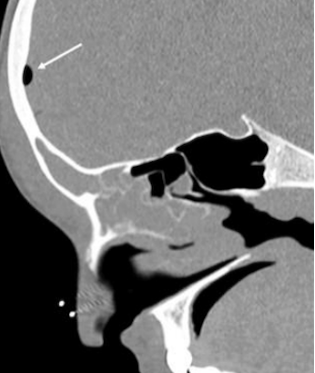

Alla luce della valutazione clinico-laboratoristica, viene posto il sospetto di sinusite frontale complicata. Vengono eseguiti una radiografia del cranio e dei seni nasali e paranasali (Figura 1) e una tomografia computerizzata (TC) dell’encefalo e del massiccio facciale.

La presenza di aria nei tessuti molli extracranici visibile radiograficamente e lo pneumocefalo riscontrato alla TC confermano il sospetto diagnostico. Viene quindi eseguito un drenaggio endoscopico del seno frontale, con raccolta del materiale purulento e coltura microbiologica. Previa esecuzione di emocolture, viene impostata una terapia antibiotica endovenosa empirica con ceftriaxone e clindamicina, seguita da miglioramento significativo della tumefazione, defervescenza e risoluzione del dolore. Gli esami ematici mostrano un graduale miglioramento fino a completa normalizzazione. Le colture rilevano la crescita di uno Streptococcus intermedius multisensibile su emocolture e sul materiale purulento.